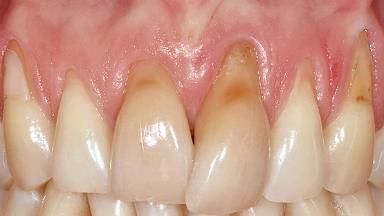

Implant Placement in the Esthetic Zone and Coverage of Multiple Gingival Recessions

This case illustrates use of a modified ‘tunnel’ technique, which has been shown to be highly effective in root coverage procedures. The tunnel technique is used to achieve soft-tissue augmentation across the anterior area, including the planned implant site, using collagen matrix as grafting material. The patient is a 47-year-old woman with high esthetic expectations. Her main concern was the appearance of the anterior teeth and their “elongation”.